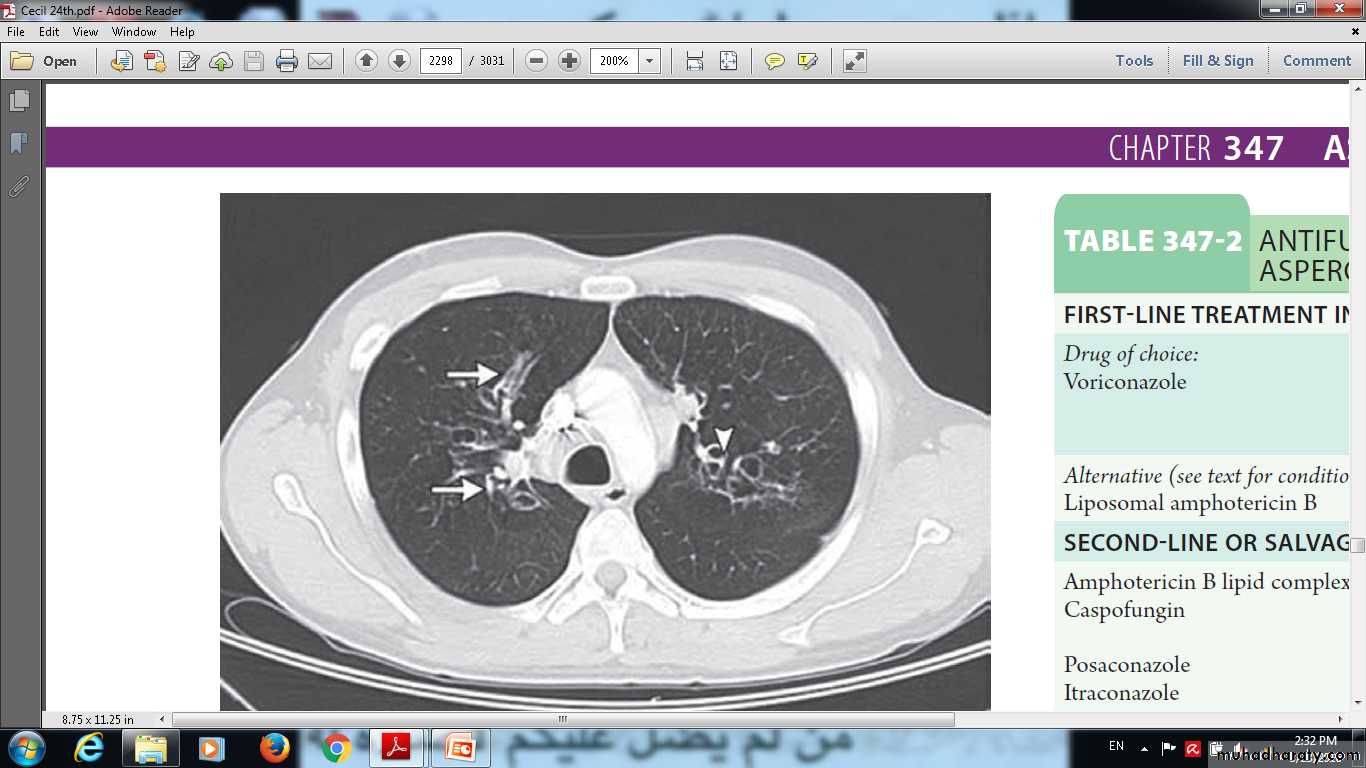

Allergic bronchopulmonary aspergillosis in a patient with a longhistory of asthma. Chest radiographs showed multilobar infiltrates. Computedtomographyshows areas of tubular ( arrows) and cystic ( arrowhead) bronchiectasis.

Allergic bronchopulmonary aspergillosis in a patient with a longhistory of asthma. Chest radiographs showed multilobar infiltrates. Allergic bronchopulmonary aspergillosis in a patient with a longhistory of asthma. Chest radiographs showed multilobar infiltrates predominantlyin the upper lobes, and bilateral mucous plugging ( arrows) with mediastinal and hilar lymphadenopathy